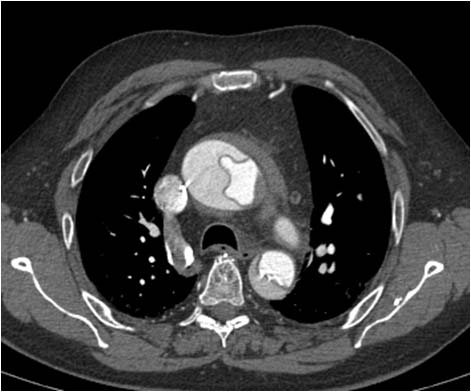

SIGNO DEL COLGAJO (O FLAP) INTIMAL

Signo de disección aórtica que puede verse tanto en ecografía, TC, resonancia magnética y arteriografía. Consiste en la presencia de una lámina -la capa íntima de la pared aórtica disecada- en el interior de la luz aórtica. En la imagen vemos un estudio de angioTC que muestra el colgajo tanto en la aorta ascendente como en la descendente. Puede distinguirse perfectamente la luz verdadera (más contrastada) de la falsa (menos densa).

SIGNO DE LA DOBLE LUZ AÓRTICA

Signo de disección aórtica visible tanto en ecografía, como en TC, resonancia y aortografía. La aorta presenta una doble luz separada por una delgada lámina (el colgajo intimal). En los estudios con contraste se demuestra que la velocidad del flujo y la densidad es mayor en la luz verdadera que en la falsa.

Imagen de aortografía en un paciente con disección. La luz verdadera está marcada con la flecha roja y la falsa con la blanca. Puede verse un ejemplo del signo en la resonancia en el Signo del colgajo (o flap) intimal.